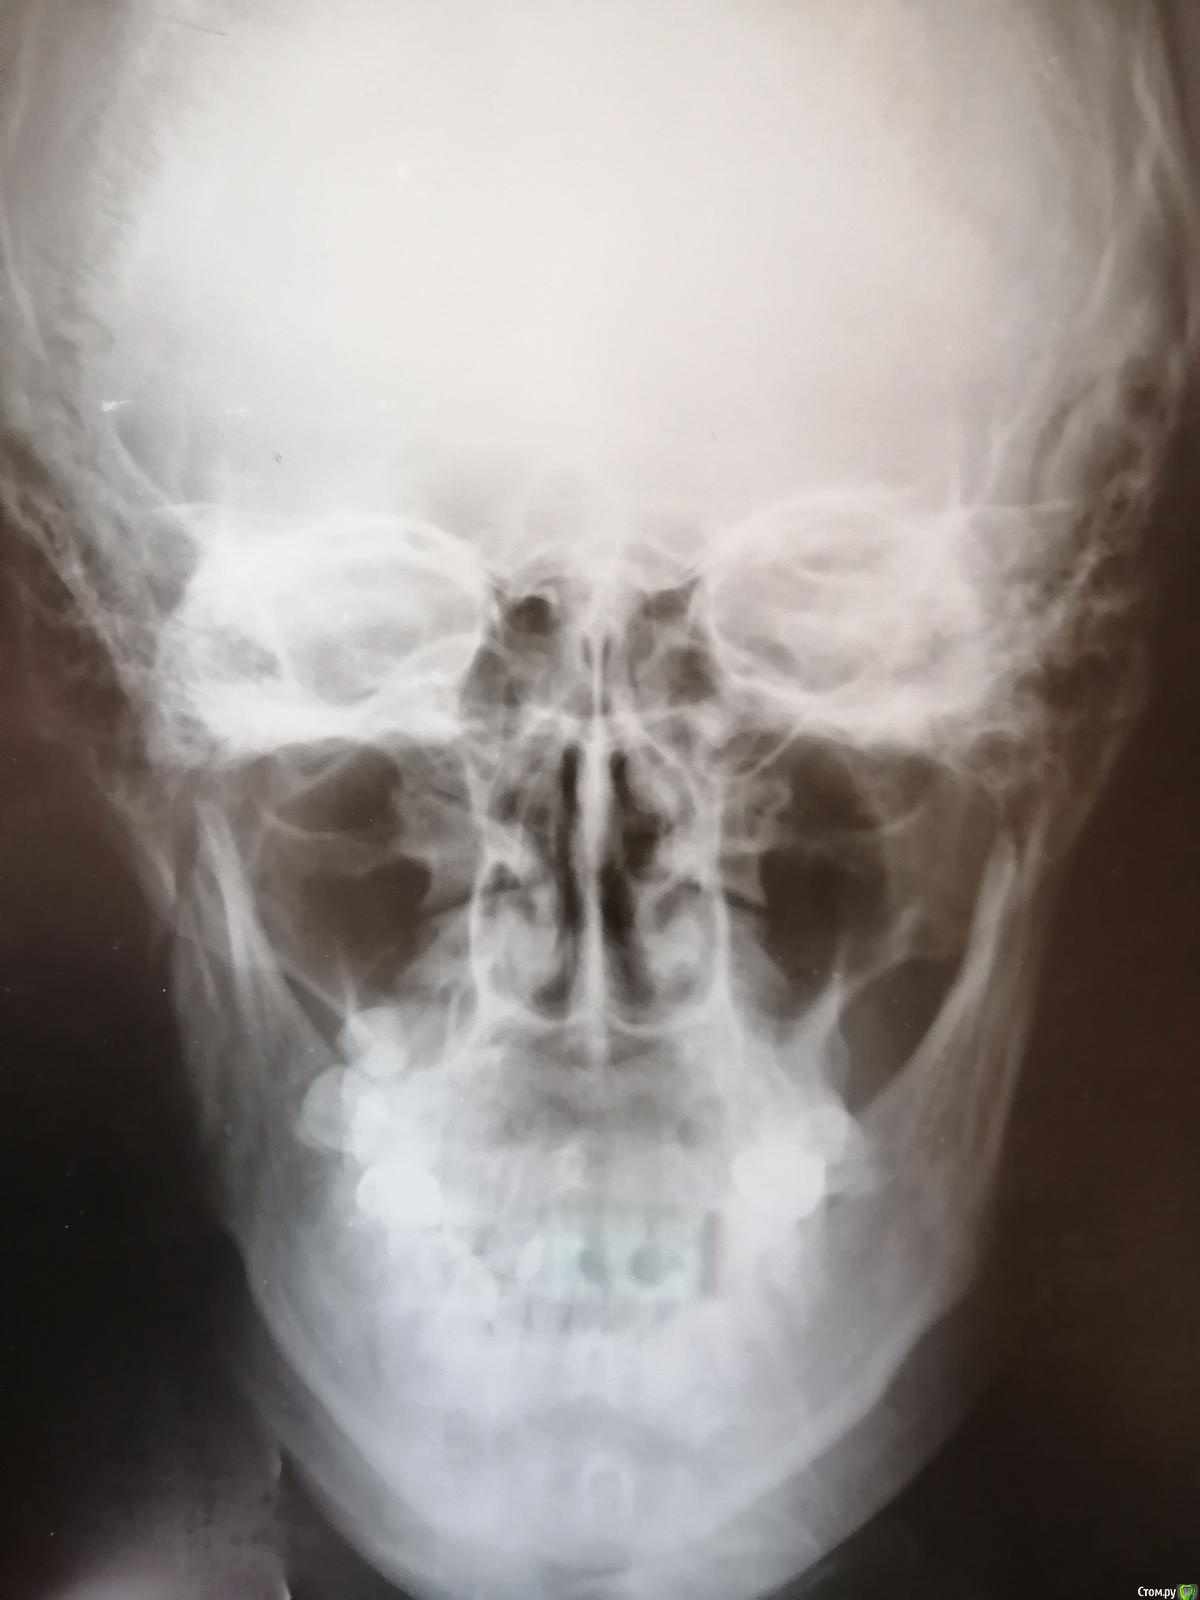

Blazingstar Опубликовано 16 июля, 2019 Поделиться Опубликовано 16 июля, 2019 (изменено) Перелом венечного отростка со смещением отломков. Сломал челюсть 16 июня прошлого месяца, обратился с болями в местную больницу к стоматологу, прописали антибиотики и сказали, что всё срастётся главное нё кушай твёрдое, потом 21 июня по собственной инициативе обратился в Члх, там сразу поставили шины если её не ставить сказали потом рот будет вонять всегда, там лежал 10 дней, в стационаре кололи антибиотики и вот сняли сегодня шины в местной больнице стоматолог посоветовал не есть три четыре дня твёрдую пищу. Во время лечения резинки не меняли ни разу когда лежал в стационаре и после в местной больнице, советовали только ромашкой полоскать. Пожалуйста посмотрите снимок срастётся ли всё нормально операцию не делали. Завтра на работу еду на вахту 15 дней. После снимок не делали. В стационаре сделали снимок зубов только спустя три дня, место перелома не снимали. Где череп это снимок до шинирования, остальные снимки после шинирования спустя три дня сделано(там не видно место перелома) . Изменено 16 июля, 2019 пользователем Blazingstar Ссылка на комментарий